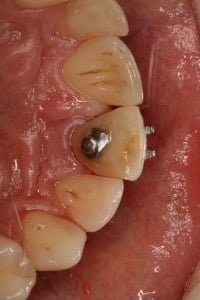

Przykład ekstruzji ortodontycznej za pomocą płytki termoformowalnej i zameczka ortodontycznego: